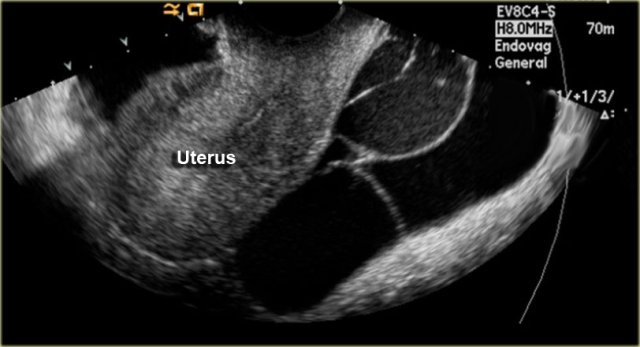

On the left a transvaginal ultrasound demonstrating a multicystic pelvic lesion next to the uterus, which proved to be a peritoneal inclusion cyst.

Sometimes the ovary is seen 'trapped' with the septate fluid collection (figure).